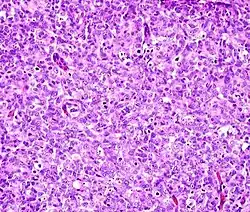

Histopathology

Micrograph showing contraction band necrosis, a histopathologic finding of myocardial infarction (heart attack).

Histopathology (compound of three Greek words: ἱστός histos 'tissue', πάθος pathos 'suffering', and -λογία -logia 'study of') is the microscopic examination of tissue in order to study the manifestations of disease. Specifically, in clinical medicine, histopathology refers to the examination of a biopsy or surgical specimen by a pathologist, after the specimen has been processed and histological sections have been placed onto glass slides. In contrast, cytopathology examines free cells or tissue micro-fragments (as "cell blocks ").